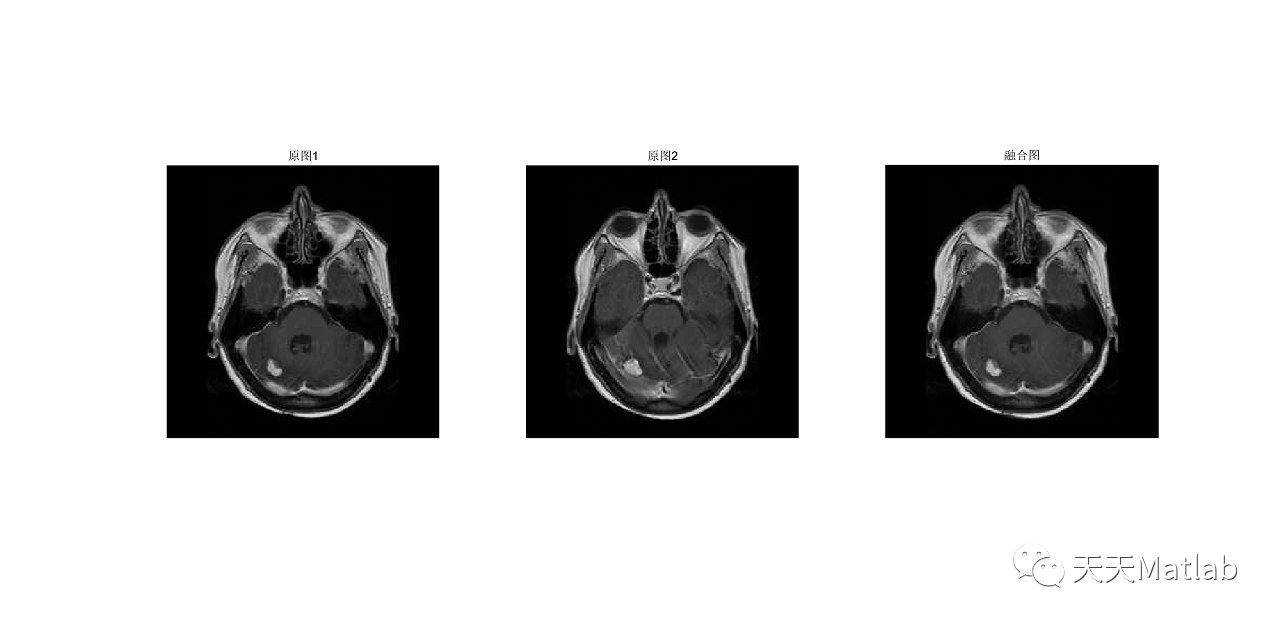

为了将低分辨率医学图像和高分辨率全色图像有效地融合,提出了主成分分析(PCA)变换和小波相结合的融合方法.小波提升后选用不同的融合规则对高低频成分进行融合,实验结果表明,该方法较好地保留了医学图像的光谱特性,提高了空间分辨率.

⛄ 运行结果

[1]邢鹏昌. 基于主成分分析变换和提升小波的图像融合[J]. 三明学院学报, 2012, 29(4):6.

PCA与小波结合的医学图像融合方法